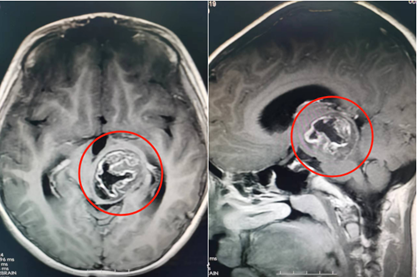

在广东三九脑科医院,医生为轩仔进行了详细检查。脑部检查结果提示,轩仔的左侧丘脑、中脑存在占位性病变,大小约为39毫米×30毫米×35毫米。该院副院长鲁明在接诊时发现,患儿左眼斜视明显、右上肢肌力下降,推断是脑肿瘤引起的症状。

术前影像资料。